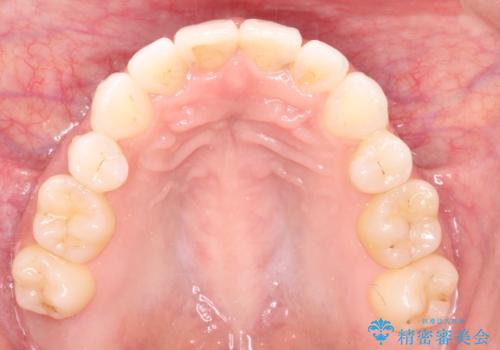

前歯の後戻りを部分矯正で整った歯並びへ

- 矯正治療後の上の前歯の後戻りを気にされて来院されました。

上の前歯のみにブラケットをつけて矯正治療を行いました。

部分矯正は、わずかなガタつき、ずれには有効的です。

ただし、場合によっては部分矯正では対応できないこともあり、その時は全体矯正が必要となります。